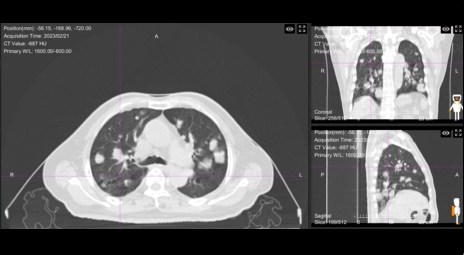

62岁的刘女士就是这项技术的受益者之一。她被确诊为肺继发恶性肿瘤(pT0N0M1 IV期),PET/CT检查显示右肺上叶有混合磨玻璃状密度增高影,代谢增高,考虑为肺转移。在传统治疗方案受限的情况下,这项全新的重离子治疗技术,为她带来了新的康复希望。